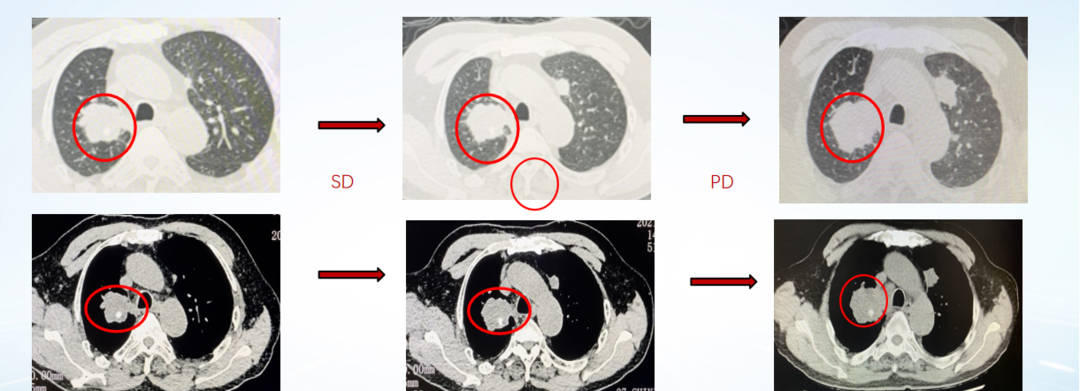

影像学评估:

图22、呋喹替尼治疗期间,患者肺部转移灶胸部增强CT评估情况:左(2020-10-23)、中(2021-05-27)、右(2021-07-06)

图23、呋喹替尼治疗期间,患者口腔颊黏膜转移灶口腔增强CT评估情况:左(2020-10-23)、中(2021-05-27)、右(2021-07-08)

疾病进展:2021年8月,患者出现咳胸闷,咳嗽。胸部CT提示双肺转移瘤相仿,右侧支气管内多发软组织密度影。

图24、胸部增强CT显示支气管内新增转移病灶:左(2021-07-06)、右(2021-08-31)